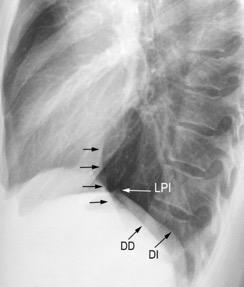

Diafragma izquierdo +/-16mm El ligamento pulmonar izquierdo (LPI) puede interrumpir la interfase normal pulmonar-diafragma obliterando un pequeño segmento

Proto AV,. The left lateral radiograph of the chest. Part One. Med. Radiogr. Photogr.1979.

Variante: Aire/grasa por delante de la VCI

Molinari F et al. Fat-containing Lesions in adult thoracic imaging. AJR.2011